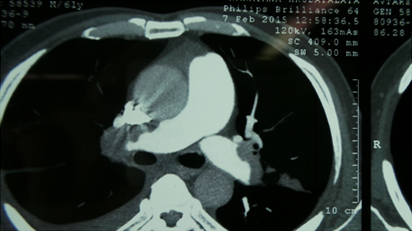

CT Pulmonary Angiography Showing Intra Pulmonary Filling defects

Filling Defects Within Pulmonary Artery